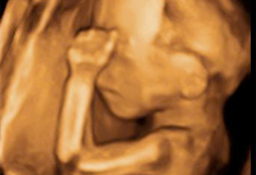

A lo largo del embarazo, el médico te recomendará una serie de pruebas diagnósticas para asegurarse que tu hijo se desarrolla correctamente, como la ecografía. Otras solo se prescriben cuando el ginecólogo sospecha que algo puede ir mal y necesita más datos para corraborarlo, como la amniocentesis o el control del bienestar fetal. Te contamos cómo y cuándo se realizan.